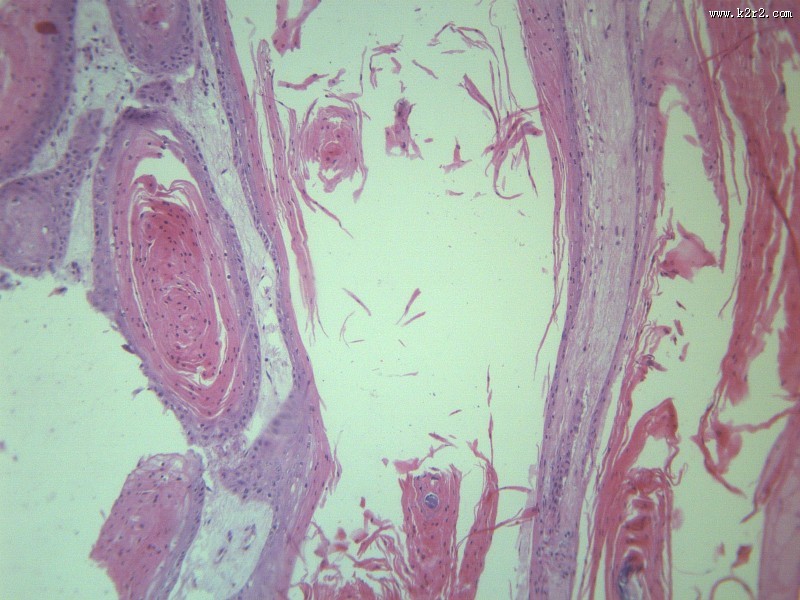

首页 > 其他类别 > 高分化鳞癌(12张) > 高分化鳞癌 第3张

高分化鳞癌 - 第3张